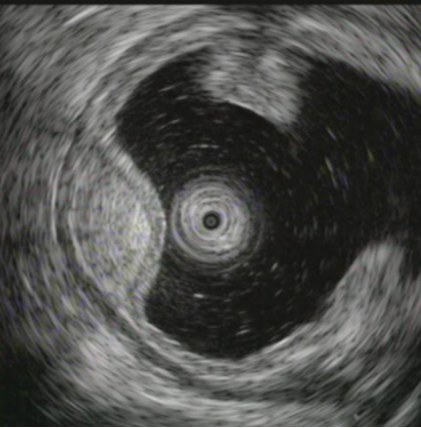

⑦超声胃镜

EUS是将微型高频超声探头安置在内镜前端,在内镜直视观察腔内形态的同时,又可进行实时超声扫描近距离探查,使靶器官的结构与图像更为清楚,为临床治疗方案的选择提供了有力的支持。我院消化内镜于2004年在四川省率先开展EUS新技术,目前拥有国内最新—代的EUS系统,它集超声内镜主机、高频小探头、三维超声探头、环扫内镜超声等 先进设备为—体。我院EUS诊疗组,现有教授1名、副教授2名,每年完成近千例消化道EUS诊疗,EUS诊疗技术达到省内先进水平。

为什么需要EUS

普通内镜检查只能发现消化道表面的病灶,通过EUS显示消化管壁层次结构及周围脏器病变,能更准确判断胃肠隆起病变的 性质、来源、肿瘤的浸润深度,还能取活检,指导确定治疗方案及判断疗效。